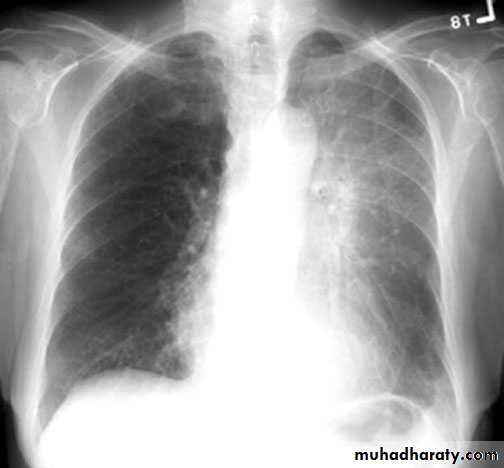

Pleural effusion ( free)

Massive pleural effusion